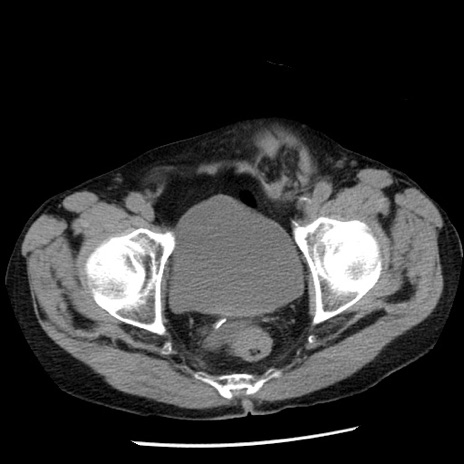

症例26(横断像)

【症例】80歳代男性

【主訴】嘔吐

【現病歴】昨晩2回嘔吐あり、今朝になっても嘔吐あり。来院。

【既往歴】胃潰瘍

【身体所見】意識清明、BT 37.6℃、BP 166/95mmHg、HR 100bpm、SpO2 97%、腹部:平坦・軟、腸蠕動音聴取良好、圧痛なし。

【データ】WBC 21900、CRP 1.46